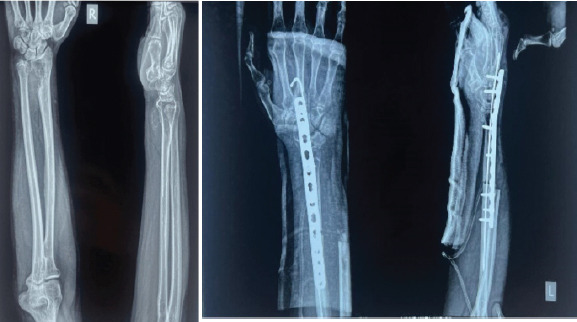

Case series: In this case series, we present surgical methodology tailored for individual characteristics of GCTs, with emphasis on functional recovery. We demonstrate four cases involving different sites GCT - tendon sheath in hand, distal ulna, distal radius, and proximal tibia. Each case was managed using a site-specific surgical approach, ranging from en bloc resection with ulna transposition and arthrodesis to Illizarov assisted bone transport. Emphasis is laid on strategic surgical technique coupled with functional preservation and prevention of recurrence. All patients were successfully treated without recurrences at follow-up ranging 6 months to 2 years. Functional outcomes varied depending on the location and extent of surgical dissection, but improved overall, as evident by patients' return to routine daily activities with significant relief from pain. This case series underscores importance of a tailored, site-specific approach for managing GCT.